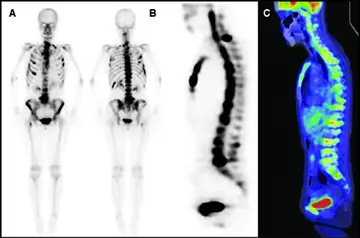

کارسینوماتوز مغز استخوان در سرطان‌ معده (۲) (بخش پایانی)

اسکن استخوان و توموگرافی با گسیل پوزیترون فلوروداکسی گلوکز ، ضایعات متاستاتیک ...

کارسینوماتوز مغزاستخوان در سرطان‌معده